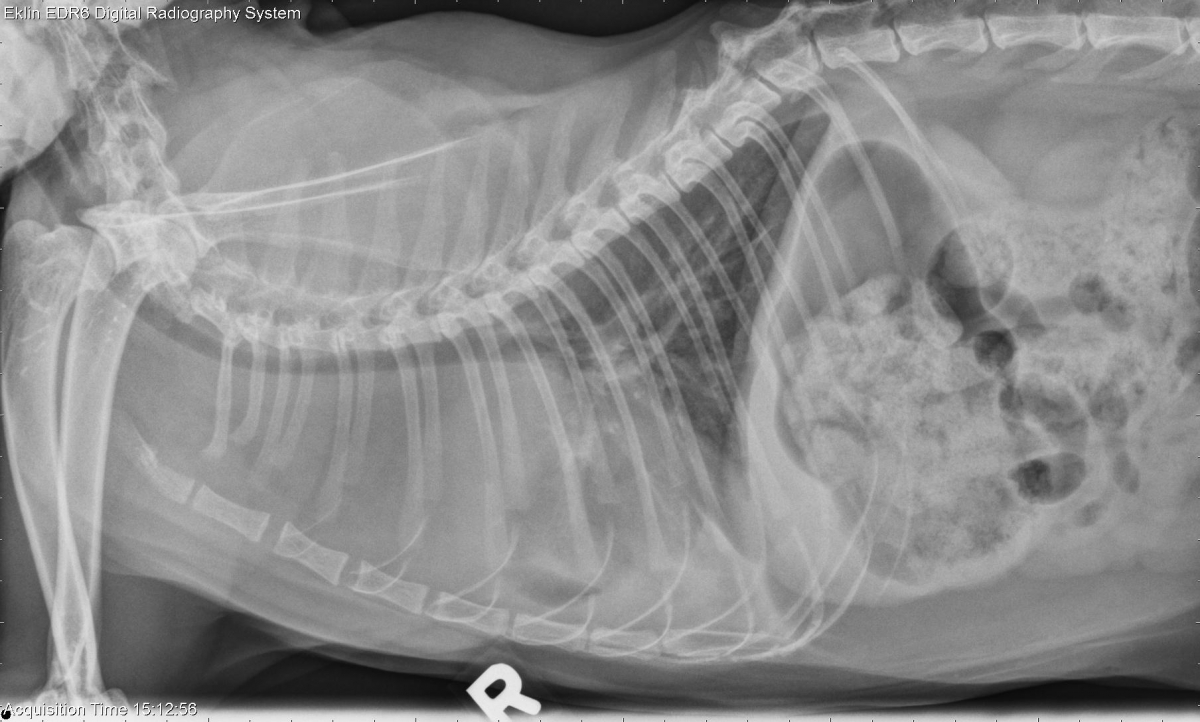

Today’s case is an 8 year old male neutered Domestic Shorthair with vomiting, decreased appetite, and respiratory distress. Where is the lesion located?

There is a large soft tissue opacity mass in the cranial thorax, centered in the cranial mediastinum. The trachea is elevated by the mass, and the heart is caudally displaced. Small pleural fissure lines are visible on the dorsoventral projection. There is collapse or compression of the cranial lung lobes and a mild interstitial pattern in the caudal lung lobes. The stomach and intestines are moderately filled with gas and food.

• Cranial mediastinal mass (lymphoma, thymoma, granuloma, cyst)

• Secondary pleural effusion and atelectasis

• Aerophagia

• Cranial mediastinal lymphoma, high grade large-cell type